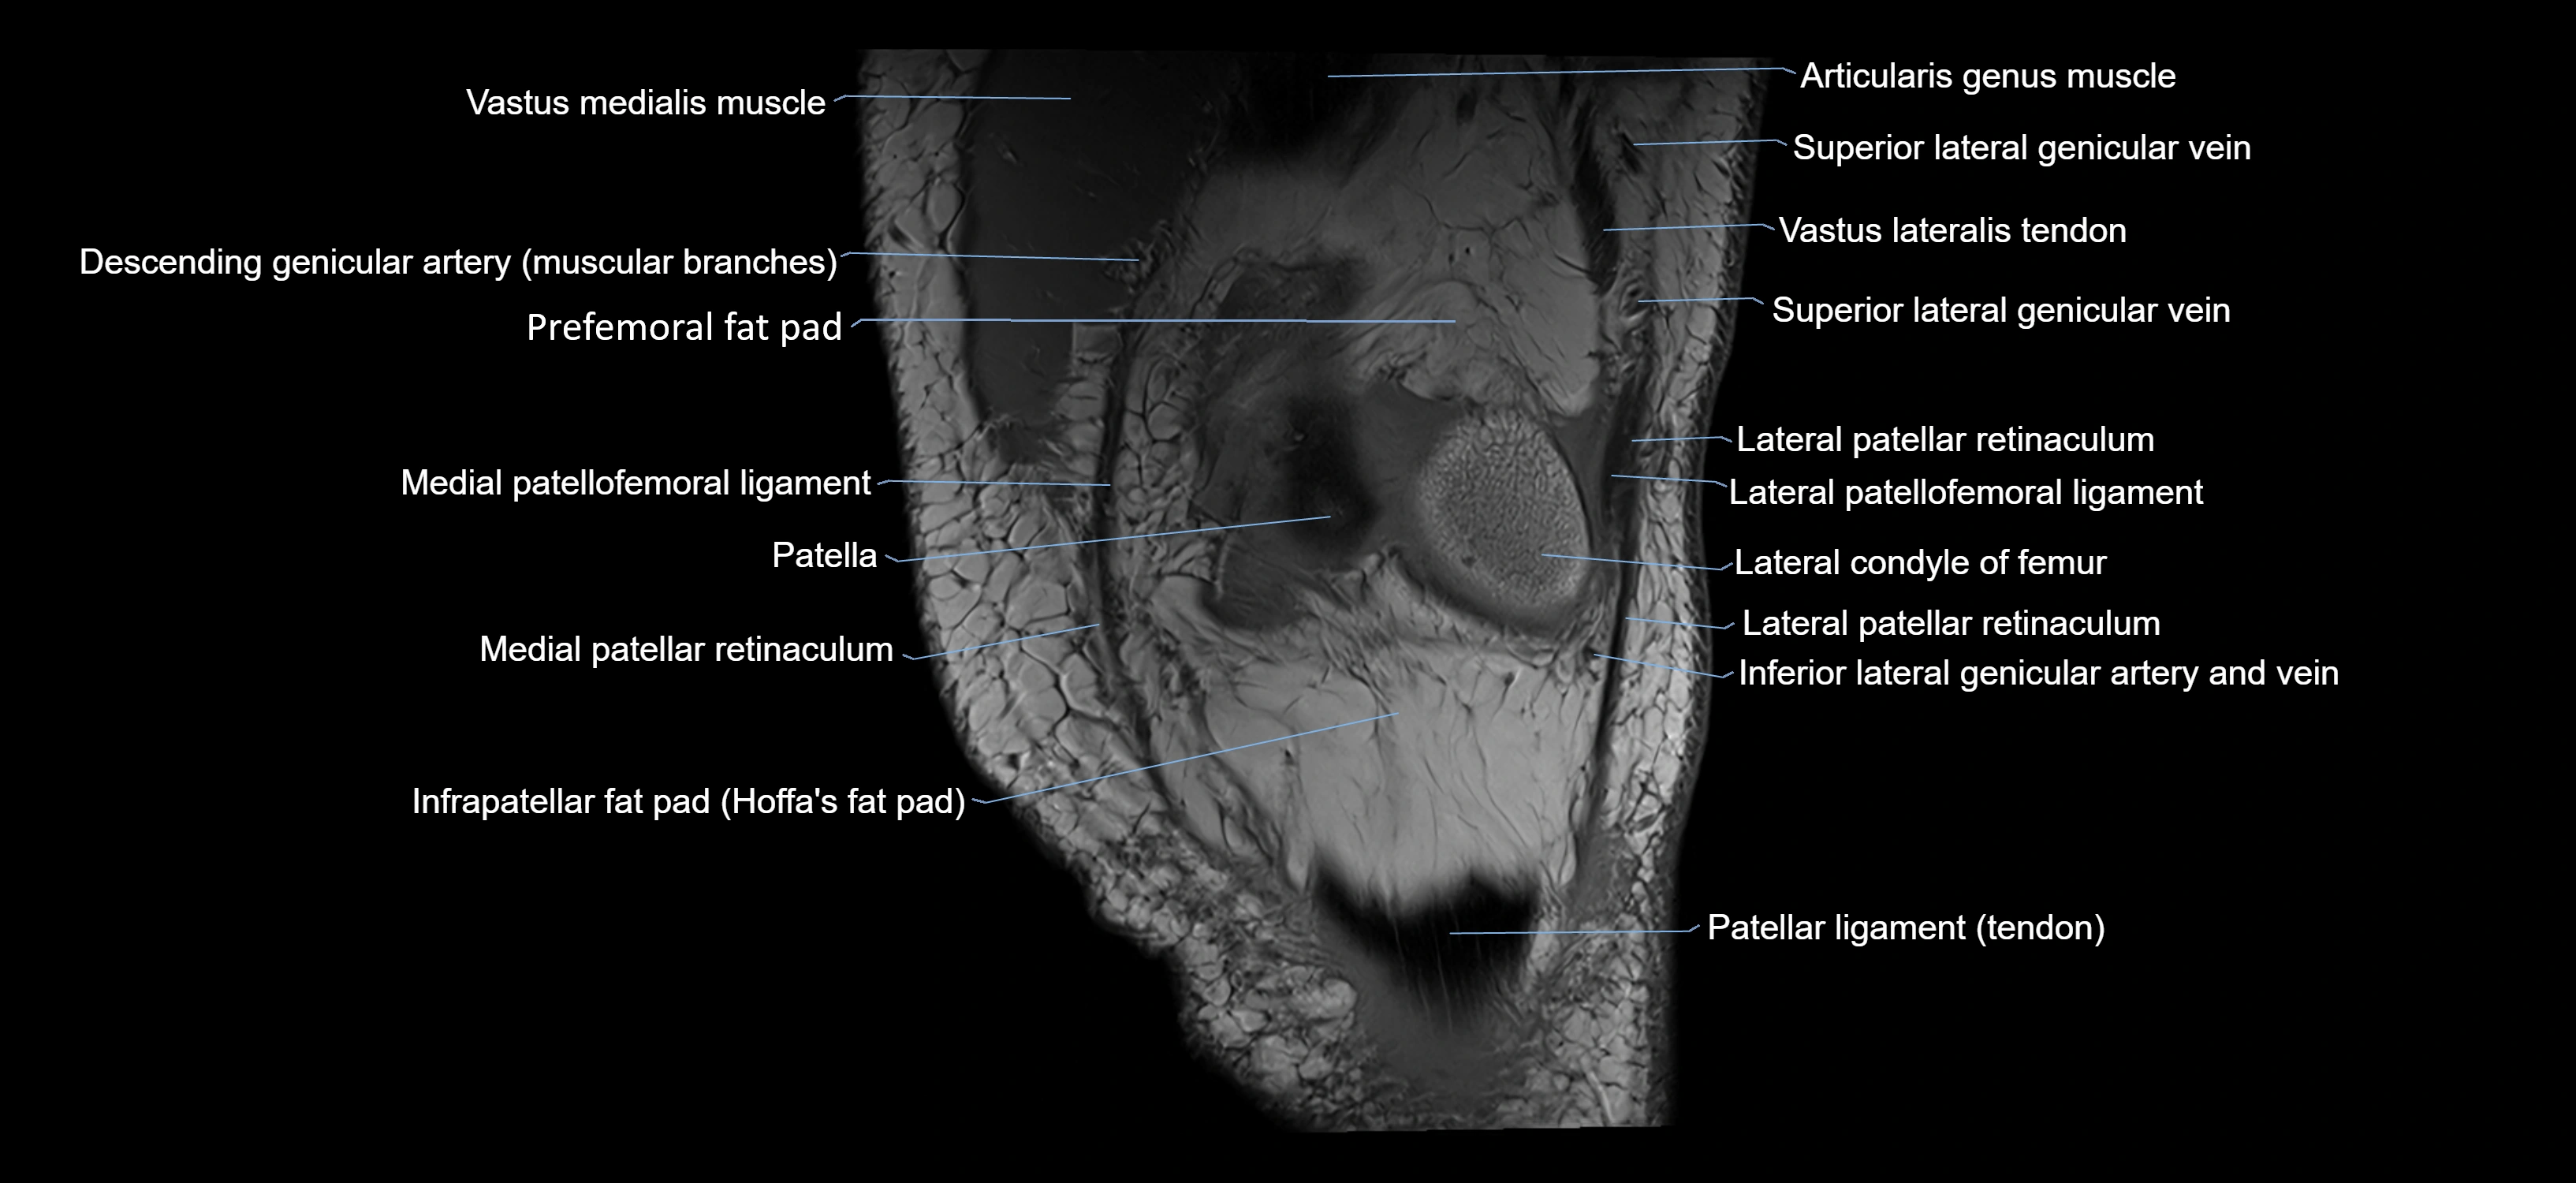

- Inferior lateral genicular artery

- Inferior lateral genicular vein

- Infrapatellar fat pad

- Lateral condyle of femur

- Lateral patellar retinaculum

- Lateral patellofemoral ligament

- Medial patellar retinaculum

- Medial patellofemoral ligament

- Patella

- Patellar articular cartilage

- Patellar tendon (patellar ligament)

- Prefemoral fat pad

- Superior lateral genicular vein

- Vastus lateralis muscle

- Vastus medialis muscle